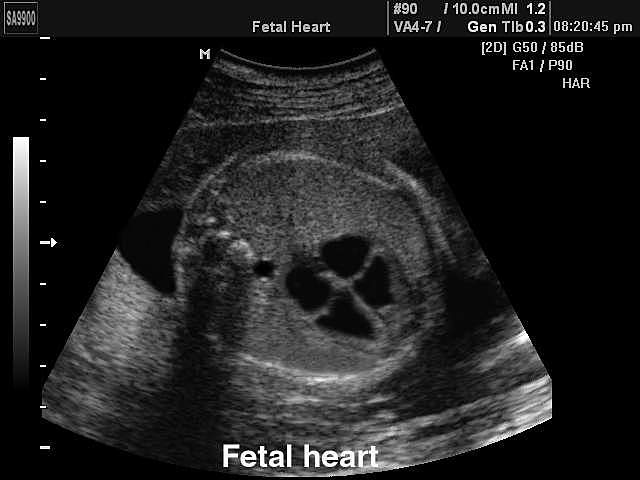

As the EMBRYO grows, the heart begins to develop. The pulse begins after about week four, once the head has developed. This is in the EMBRYONIC STAGE.

Photo:

http://telling-secrets.blogspot.com/2013/03/take-breath.html -